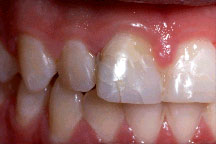

En este paciente, el incisivo superior presentaba una fractura traumática y fue tratado endodónticamente. Nótese el gran espacio radicular debido al diente inmaduro, ápice abierto.

El diente fue tratado endodónticamente con apexificación utilizando hidróxido de calcio y luego se rellenó con gutapercha. Observe el gran espacio del canal y la delgada estructura interior del diente.